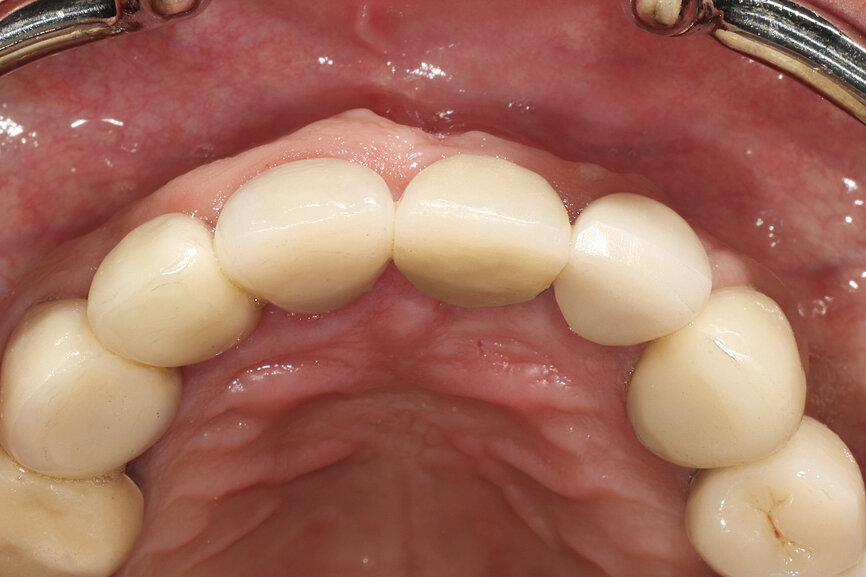

Fig. 29: The definitive restoration exhibited excellent retention of the soft-tissue profile.

Fig. 30a: The occlusal view revealed the volume maintained with

the soft-tissue cervical contours (a), and the lateral retracted view revealed an excellent soft-tissue emergence profile (b).

Fig. 30b: The occlusal view revealed the volume maintained with

The initial plan was for immediate extraction, immediate placement and immediate restoration. Therefore, it was essential to measure the implant’s stability with an objective technology, RFA, which provides an ISQ value utilising an implant-specific SmartPeg (Osstell; MEGA ISQ, MegaGen). The baseline ISQ value (76) confirmed sufficient initial stability to place an immediate restoration (Fig. 25). The prefabricated CAD/CAM abutment was then secured to the implant, and a postoperative periapical radiograph confirmed successful sub-crestal placement for this platform-switched design (Fig. 26a). The transitional acrylic restoration was then placed and examined for any occlusal interferences (Fig. 26b). It was important that the restoration be out of occlusion to avoid premature forces that could complicate integration. The soft-tissue contours were excellent, and no sutures were required, since no flap was raised (Figs. 26c & d). After a period of eight weeks, the implant stability was measured to be at 80 ISQ, confirming that the integration process had continued to progress successfully and that the implant was ready for the definitive restoration. An intra-oral scanner and scanning abutment were then utilised to capture the position of the implant and soft-tissue emergence profile. The post- operative CBCT scan revealed the intact crescent shape of the root membrane (Figs. 27 & 28). The definitive restoration was then delivered and exhibited excellent retention of the soft-tissue profile (Figs. 29 & 30).